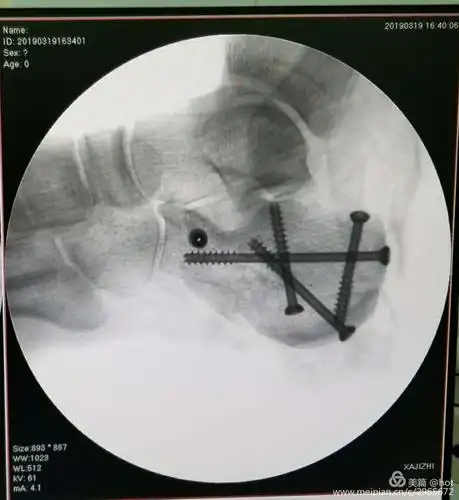

跟骨骨折经皮撬拨复位空心螺钉内固定术